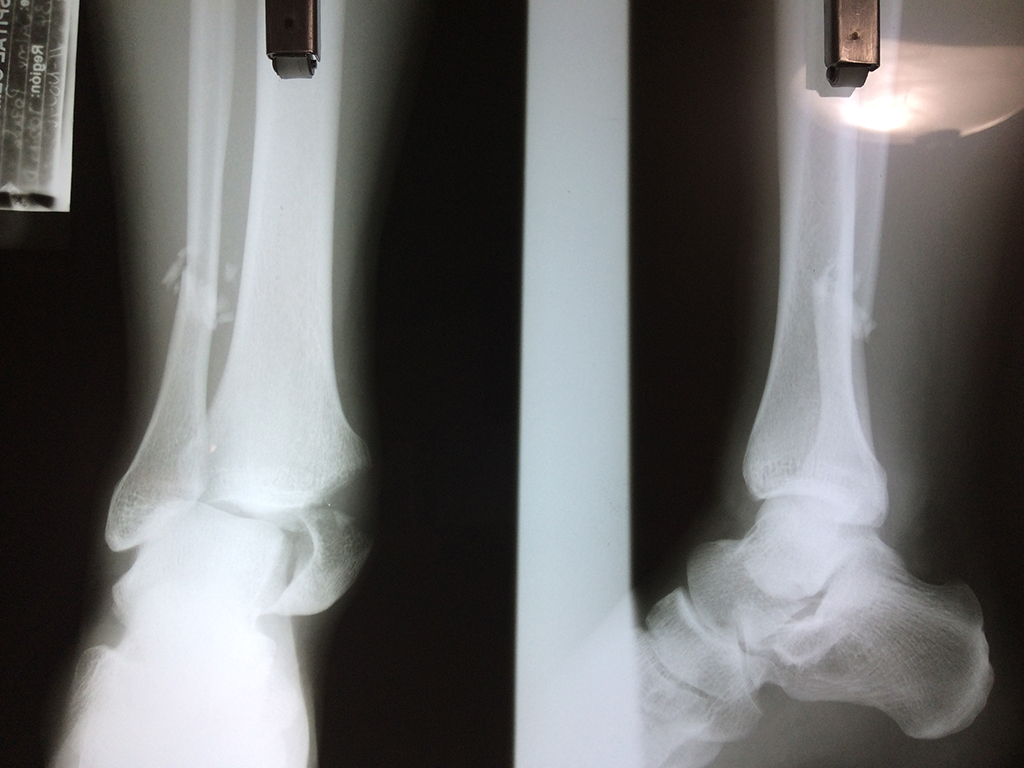

Una fractura de tobillo es la rotura de uno o más de los huesos del tobillo. Estas fracturas pueden ser:

- Parciales (el hueso está sólo parcialmente fisurado, no del todo).

- Completas (el hueso está perforado y está en 2 partes).